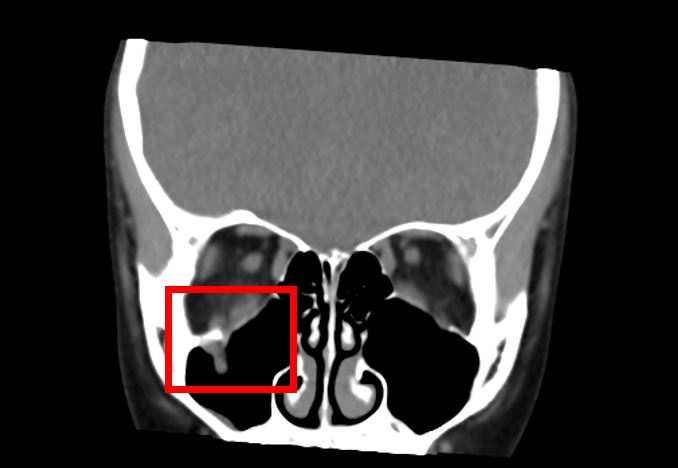

中山醫學大學附設醫院口腔顎面外科醫師邱昱瑋指出,眼窩骨折常見於眼眶底部,多因直徑大於眼球的鈍器撞擊,例如棒球、拳頭或意外碰撞,造成較薄的眶底骨因力量傳導而破裂。經診斷,9歲女童的眼底破損,眼窩組織掉入上顎竇,造成眼球往上轉動受到影響。

尤其兒童的骨頭相對柔軟,更容易發生所謂「線性爆裂性骨折」,這種骨折機制如同門片回彈復位,容易將眼眶內的肌肉或其他軟組織嵌頓在骨折縫隙中,導致複視及眼球運動受限。